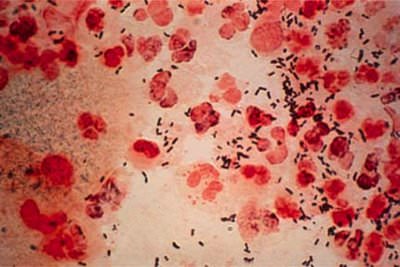

Диагностика гонореи

Для уточнения диагноза назначают следующие лабораторные исследования:

- посев мазка на питательную среду. Берут выделения из прямой кишки и уретры, а также секрет простаты;

- бактериологическое исследование мазка из уретры;